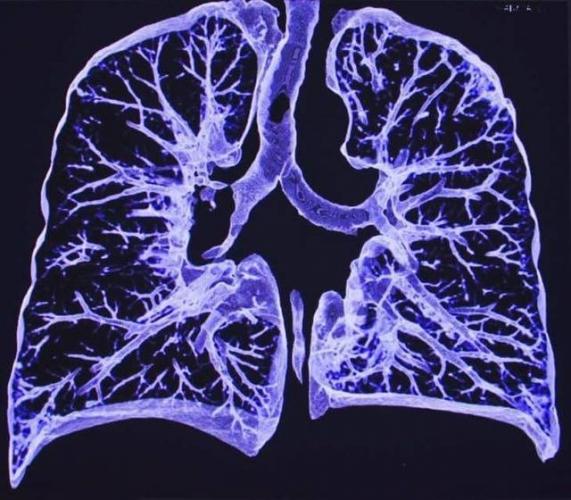

- Сделать рентген (к сожалению, пока не в каждой больнице есть аппаратура для обследования лежачих больных). Скопившаяся в лёгких жидкость на плёнке даст тени и уменьшение прозрачности, но «картинка» будет неотличима от других лёгочных болезней – например, бронхопневмонии.

- Провести УЗИ плевральной полости для уточнения результата, определения наличия жидкости и её локализации.

- рентгенография органов грудной клетки;

- компьютерная или магнитно-резонансная томография (при необходимости);